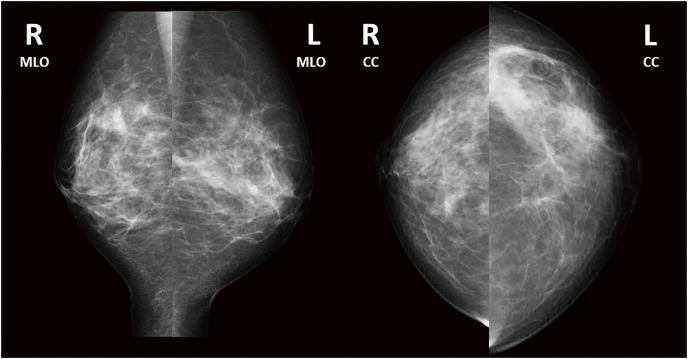

Case presentation: We report the case of a 36-year-old Japanese woman with granulomatous mastitis due to Mycobacteroides abscessus who had not undergone surgery and was not immunosuppressed. She presented with a chief complaint of pain and swelling in her left breast for 1 month. Mammography showed asymmetrical focal increased density, and ultrasonography showed an irregular hypoechoic area in the left 3 o'clock position. Contrast-enhanced magnetic resonance imaging showed segmental non-mass-enhancement. Ultrasound-guided vacuum-assisted biopsy with pathology revealed granulomatous mastitis. Ziehl-Neelsen staining revealed red-staining bacilli. The patient was followed up for observation because her breast pain had decreased after the examination, and there was no redness or fever. However, the breast pain has not completely disappeared, and intermittent purulent discharge from the biopsy site persisted for 5 months. Hence, two 12-Fr drains were inserted along the ductal dilatation-like hypoechoic area. Imipenem, amikacin, and clarithromycin were administered for 8 days. After 8 days of this therapy, the patient developed a drug-associated rash; therefore, antimicrobial therapy was discontinued, and the drains were removed. Her symptoms improved, and magnetic resonance imaging after 1 month showed that the previous imaging findings in her left breast had disappeared. At the time of writing, 18 months have passed since treatment, and no recurrence has been observed.